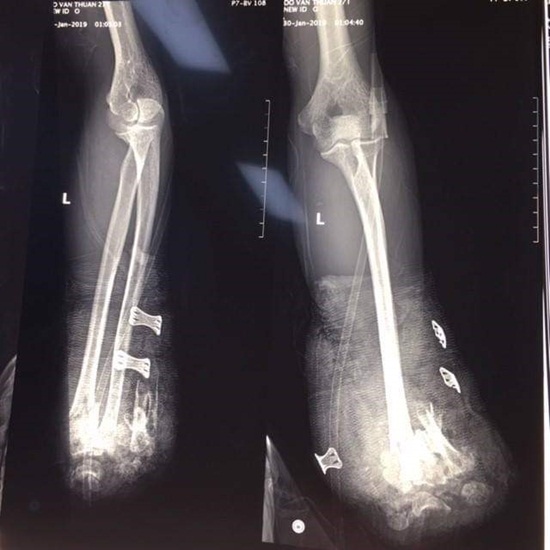

Thông tin từ Bệnh viện Trung ương Quân đội 108 cho biết, các bác sĩ Khoa Cấp cứu mới đây đã tiếp nhận bệnh nhân Đỗ Văn T (25 tuổi, ở Hải Phòng) chuyển đến viện trong tình trạng cụt 2 bàn tay, vết thương vùng hàm mặt, chảy nhiều máu vì tai nạn do pháo nổ tự chế.

Bệnh nhân được đưa tới bệnh viện trong tình trạng cụt bàn tay 2 bên, gãy hở xương hàm dưới, chấn thương ngực kín, dập nhu mô thuỳ trên hai phổi, bỏng rộng vùng ngực, nhiều vết thương nhỏ ở 2 chân.

Các bác sĩ đã mổ cấp cứu cắt cụt để ngỏ 1/3 giữa cẳng tay phải, cắt lọc cơ dập nát cẳng tay trái, kết xương hàm dưới. Sau mổ, bệnh nhân phải điều trị tiếp tại khoa Hồi sức tích cực của bệnh viện. Hiện sức khỏe bệnh nhân đã ổn định.